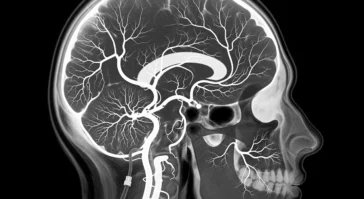

in BrainsBrain Angiography: Understanding Life-Saving Diagnostic Procedure